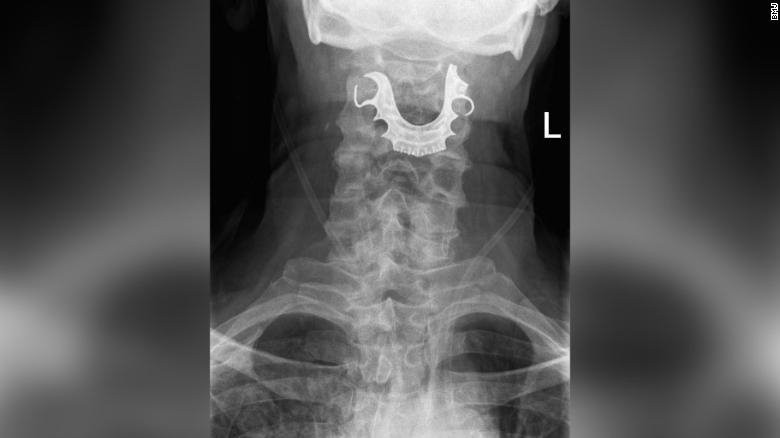

Phim chụp hàm răng giả mắc kẹt trong cổ họng bệnh nhân người Anh. Ảnh: CNN.

Ban đầu, bác sĩ không chẩn đoán ra bệnh. Họ kê đơn thuốc súc miệng, kháng sinh và chống viêm. Hai ngày sau, bệnh nhân quay lại, triệu chứng xấu đi và phải nhập viện vì nghi ngờ viêm phổi do nhiễm trùng nghiêm trọng. Cuối cùng, bác sĩ phát hiện một vật thể hình bán nguyệt chèn ngang dây thanh quản của cụ, gây sưng tấy.